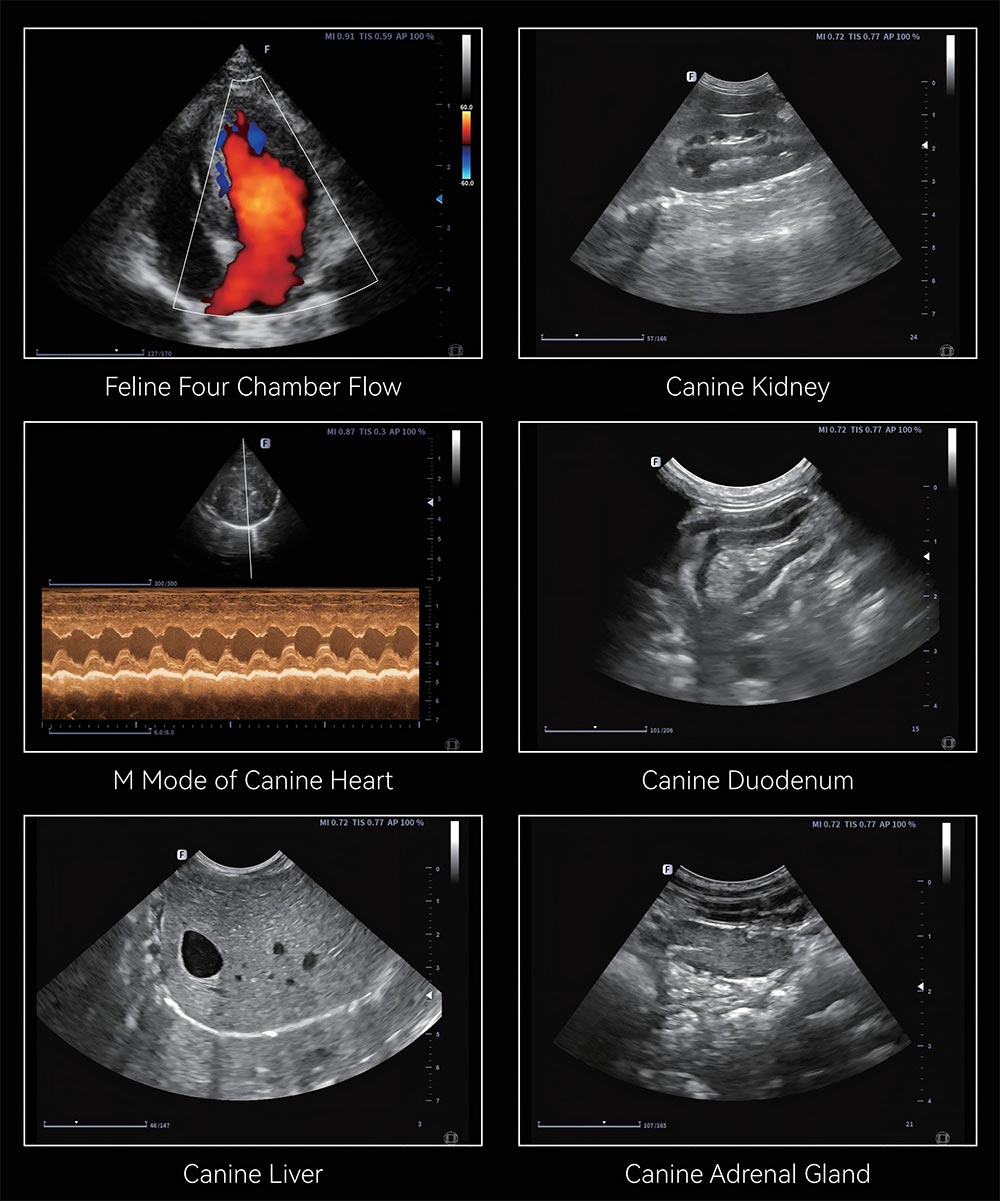

تتميز آلة الموجات فوق الصوتية البيطرية عالية الجودة من مصنع HTSY® بأنها أداة خفيفة الوزن وعالية الأداء وسهلة الاستخدام حقًا. فهو يتيح للأطباء البيطريين رؤية الهياكل الداخلية لمجموعة واسعة من الحيوانات بوضوح، مثل الكلاب والقطط والأبقار والأغنام وغيرها. يسمح نظام الموجات فوق الصوتية هذا بإجراء اختبارات سريعة ومستهدفة للمناطق الرئيسية مثل البطن والقلب، ويعمل بشكل جيد أيضًا في الممارسة السريرية الروتينية والتدريس والبحث. لقد أعطت HTSY® منذ فترة طويلة الأولوية لصحة الحيوان والتقدم في الطب البيطري، وتبذل جهودها في صياغة أدوات احترافية عملية وموثوقة للأطباء البيطريين السريريين. طلب عرض أسعار!

تستخدم آلة الموجات فوق الصوتية البيطرية الأحدث مبيعًا HTSY® غلافًا قويًا وخفيف الوزن من الألومنيوم والمغنيسيوم، مع شاشة عالية الوضوح مقاس 15.6 بوصة تعرض صورًا واضحة ومفصلة. لأنه يأتي مع إعدادات مسبقة تم تكوينها مسبقًا لمجموعة واسعة مجموعة من الأنواع الحيوانية ويدعم التوافق مع العديد من المجسات المهنية، مما يمكنه من الأداء فحوصات على الحيوانات بجميع أحجامها. يعمل نظام التصوير المحسّن الخاص بها على تقليل ضوضاء الصورة بشكل فعال وينتج صورًا أكثر وضوحًا مرئيات، مما يسمح للأطباء البيطريين بتمييز تفاصيل الأنسجة الدقيقة والتغيرات الطفيفة بسهولة. عندما تستخدم مع عجلات عند الوقوف، تتحرك الآلة وتعمل بسهولة في العيادات والمزارع، مما يجعل العمل البيطري اليومي أكثر مرونة.

تستخدم آلة الموجات فوق الصوتية البيطرية HTSY® نظام تصوير عالي الدقة مدمجًا مع تحسين الصورة العملي ميزات لإنتاج صور ديناميكية مستقرة وحادة. مع هذا المستوى من الوضوح، يمكن للأطباء البيطريين إجراء فحص أكثر دقة الهياكل الداخلية الدقيقة للأعضاء الحيوانية وتحديد التشوهات الدقيقة أثناء إجراءات التشخيص.

توفر آلة الموجات فوق الصوتية البيطرية HTSY® مجموعة متنوعة من المجسات المخصصة من المصفوفة الخطية إلى المصفوفة المرحلية، القادرة على التعامل مع مواقع التفتيش المختلفة للحيوانات الأليفة الصغيرة والماشية الكبيرة. إنه يلبي تمامًا الاحتياجات التشخيصية المتنوعة في الممارسة السريرية.